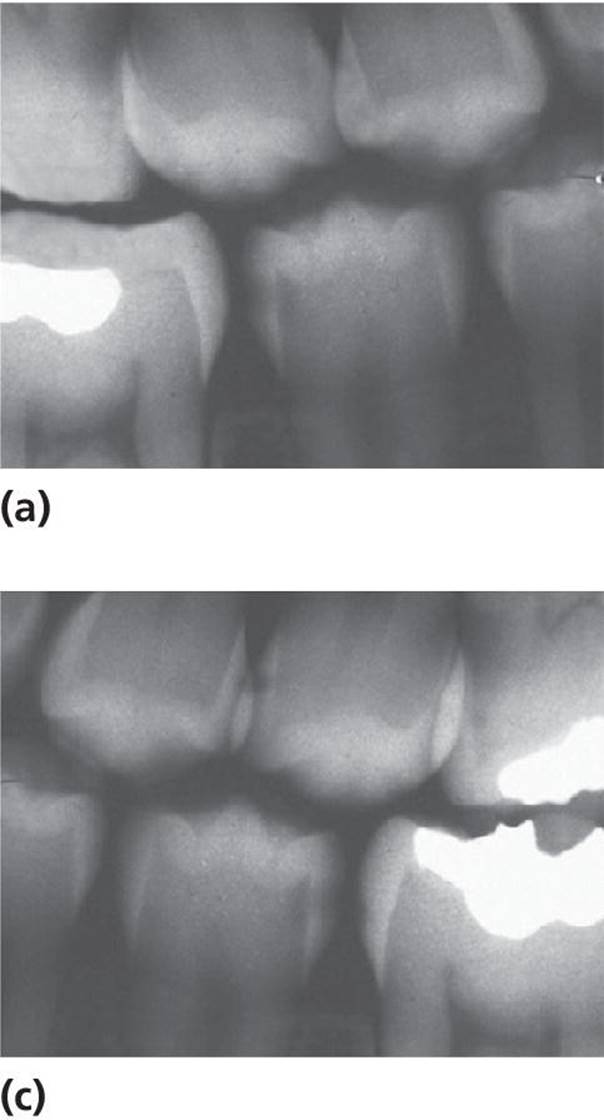

For an approximal caries lesion contacting a neighboring tooth, the border between nonoperative and restorative treatment is the presence of an obvious clinical cavity on the tooth surface. This diagnostic decision is therefore crucial. However, on this matter the radiograph does not give straightforward information. An example of this is shown in Figure 12.7, where only one of two lesions with similar radiographic appearance had a clinical cavity. Studies comparing the radiographic and clinical appearance of approximal lesions in children and young adults report great variation. The percentage of clinical cavities of surfaces with radiolucencies in the outer half of the dentin varies between 41 and 100%, the median (mean) values being 78% [12–18]. The most likely reasons for this variation are different methods used to record the presence of a cavity, different depths of the lesions investigated, and different populations with different caries activity in the various studies. It is obvious, however, that the deeper the lesion, the more likely is cavitation.

Figure 12.7 Caries lesions on distal surfaces of two mandibular second premolars: both radiographs (a and c) showed radiolucency in outer dentin, but during cavity preparation, a clinical cavity was observed only in one of them (b).